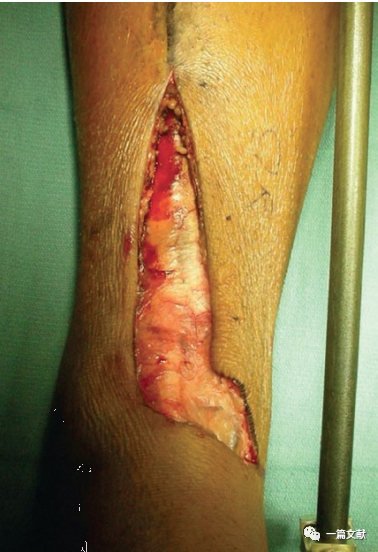

最后,深层组织闭合至关重要,先用可吸收缝线将深层组织缝合,并统一打结,这样有助于分散软组织缝合张力,避免软组织的撕裂。随后用Allgöwer-Donati法闭合手术切口,避免切口边缘皮肤坏死。如下图: